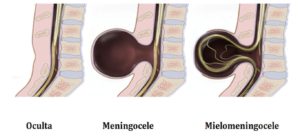

La Espina Bífida se manifiesta de tres formas y cada una de ellas se presenta con una gravedad distinta.

ESPINA BÍFIDA OCULTA:

La forma más leve produce una pequeña separación o un pequeño hueco en uno o más de los huesos (vértebras) de la columna vertebral. Debido a que los nervios raquídeos generalmente no están afectados, la mayoría de los niños con esta forma de espina bífida no tienen ningún signo ni síntoma, y no experimentan ningún problema neurológico.

ESPINA BÍFIDA QUÍSTICA O TUMORAL

Es el tipo más grave, la lesión suele apreciarse claramente como un abultamiento en forma de quiste que se sale en la zona de la espalda y se distinguen varios tipos:

- Meningocele

- Mielomeningocele

MENINGOCELE

En el caso de esta forma poco frecuente, las membranas protectoras que rodean la médula espinal (meninges) sobresalen a través de la abertura de las vértebras.

MIELOMENINGOCELE

También conocido como espina bífida abierta, el mielomeningocele es la forma de espina bífida más grave y la forma a la que las personas se refieren, por lo general, cuando usan el término espina bífida.